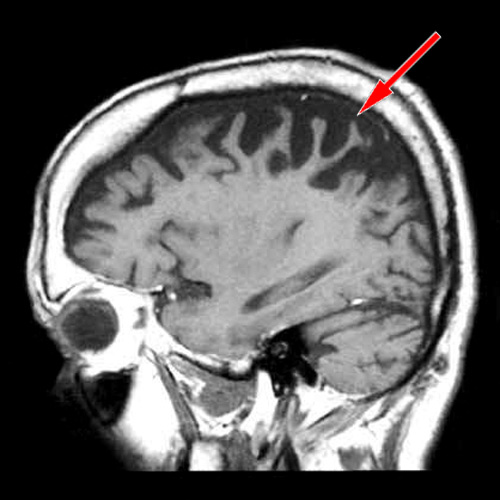

MRI nachází fokální, často výraznou a asymetrickou, atrofii především v parietální oblasti, někdy i frontálně.